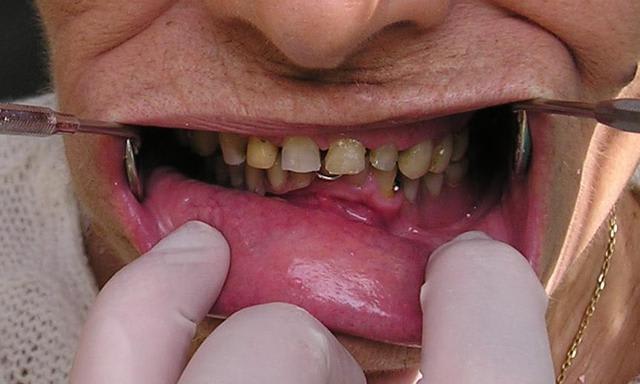

Mon premier complet immédiat sur implants fait cette semaine...

Implants posés mercredi matin, bridge posé jeudi matin...

Blague à part, son appareil à 15 ans, il veut la même chose en haut qu'en bas... pas d'os... je suis en train de me creuser la tête pour trouver une solution convenable.